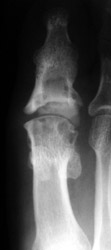

Silastic Hemiarthroplasty with large erosions 1st MT head, status post fusion 1st IP jointSILASTIC ARTHROPATHY is due to foreign body reaction to silicone particles.

2. Erosion pattern: The most common finding is the presence of erosion and osteolysis of bone adjacent to the implant.

The presence of a silastic implant is a clue to the correct diagnosis.